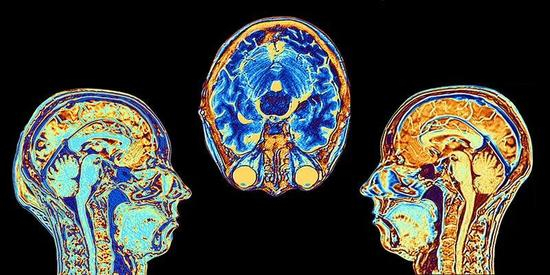

大脑是宇宙中最复杂的系统之一,已成为科研界下一个必争之地。自2013年起,美国、欧洲、日本、韩国等相继启动大型脑科学项目,中国于2016年也计划推出相关项目。4月5日,《Nature》杂志发表题为“Beijing launches pioneering brain-science centre”的文章,表示备受期待的中国脑科学计划正式落地。

顶级神经科学家聚集、动物模型供应充足、国家脑精神疾病负担以及在脑成像设施构建等一系列因素加快中国脑计划的实行。“大脑是一个复杂的系统,”欧洲人脑项目科学研究总监Katrin Amunts表示,“中国的工作有可能为其他项目提供重要的见解。”

北京中心将成为北京首屈一指的生物医学机构,它将支持使用最新生物医学方法的项目,例如高通量单基因测序、精确基因组编辑和大数据处理。罗敏敏还希望能够开发更好的成像工具,如可直接记录神经元活动的电压传感器和高速成像显微镜,以便详细了解大脑活动。

与此同时,其他中心也正在积极支持中国大脑计划。2015年,上海率先启动的“以脑科学为基础的人工智能”项目,组织科研人员开展以应用和产业为导向的协同创新,并积极参与我国国家重大科技项目。项目首席科学家、复旦大学脑力激励科学与技术研究所所长冯建峰介绍道,他们的一个重点是使用人工智能(AI)研究脑部疾病。他还补充说,人工智能算法可以筛选图像,比较患病大脑和健康大脑,以形成世界上最大大脑数据库的一部分。